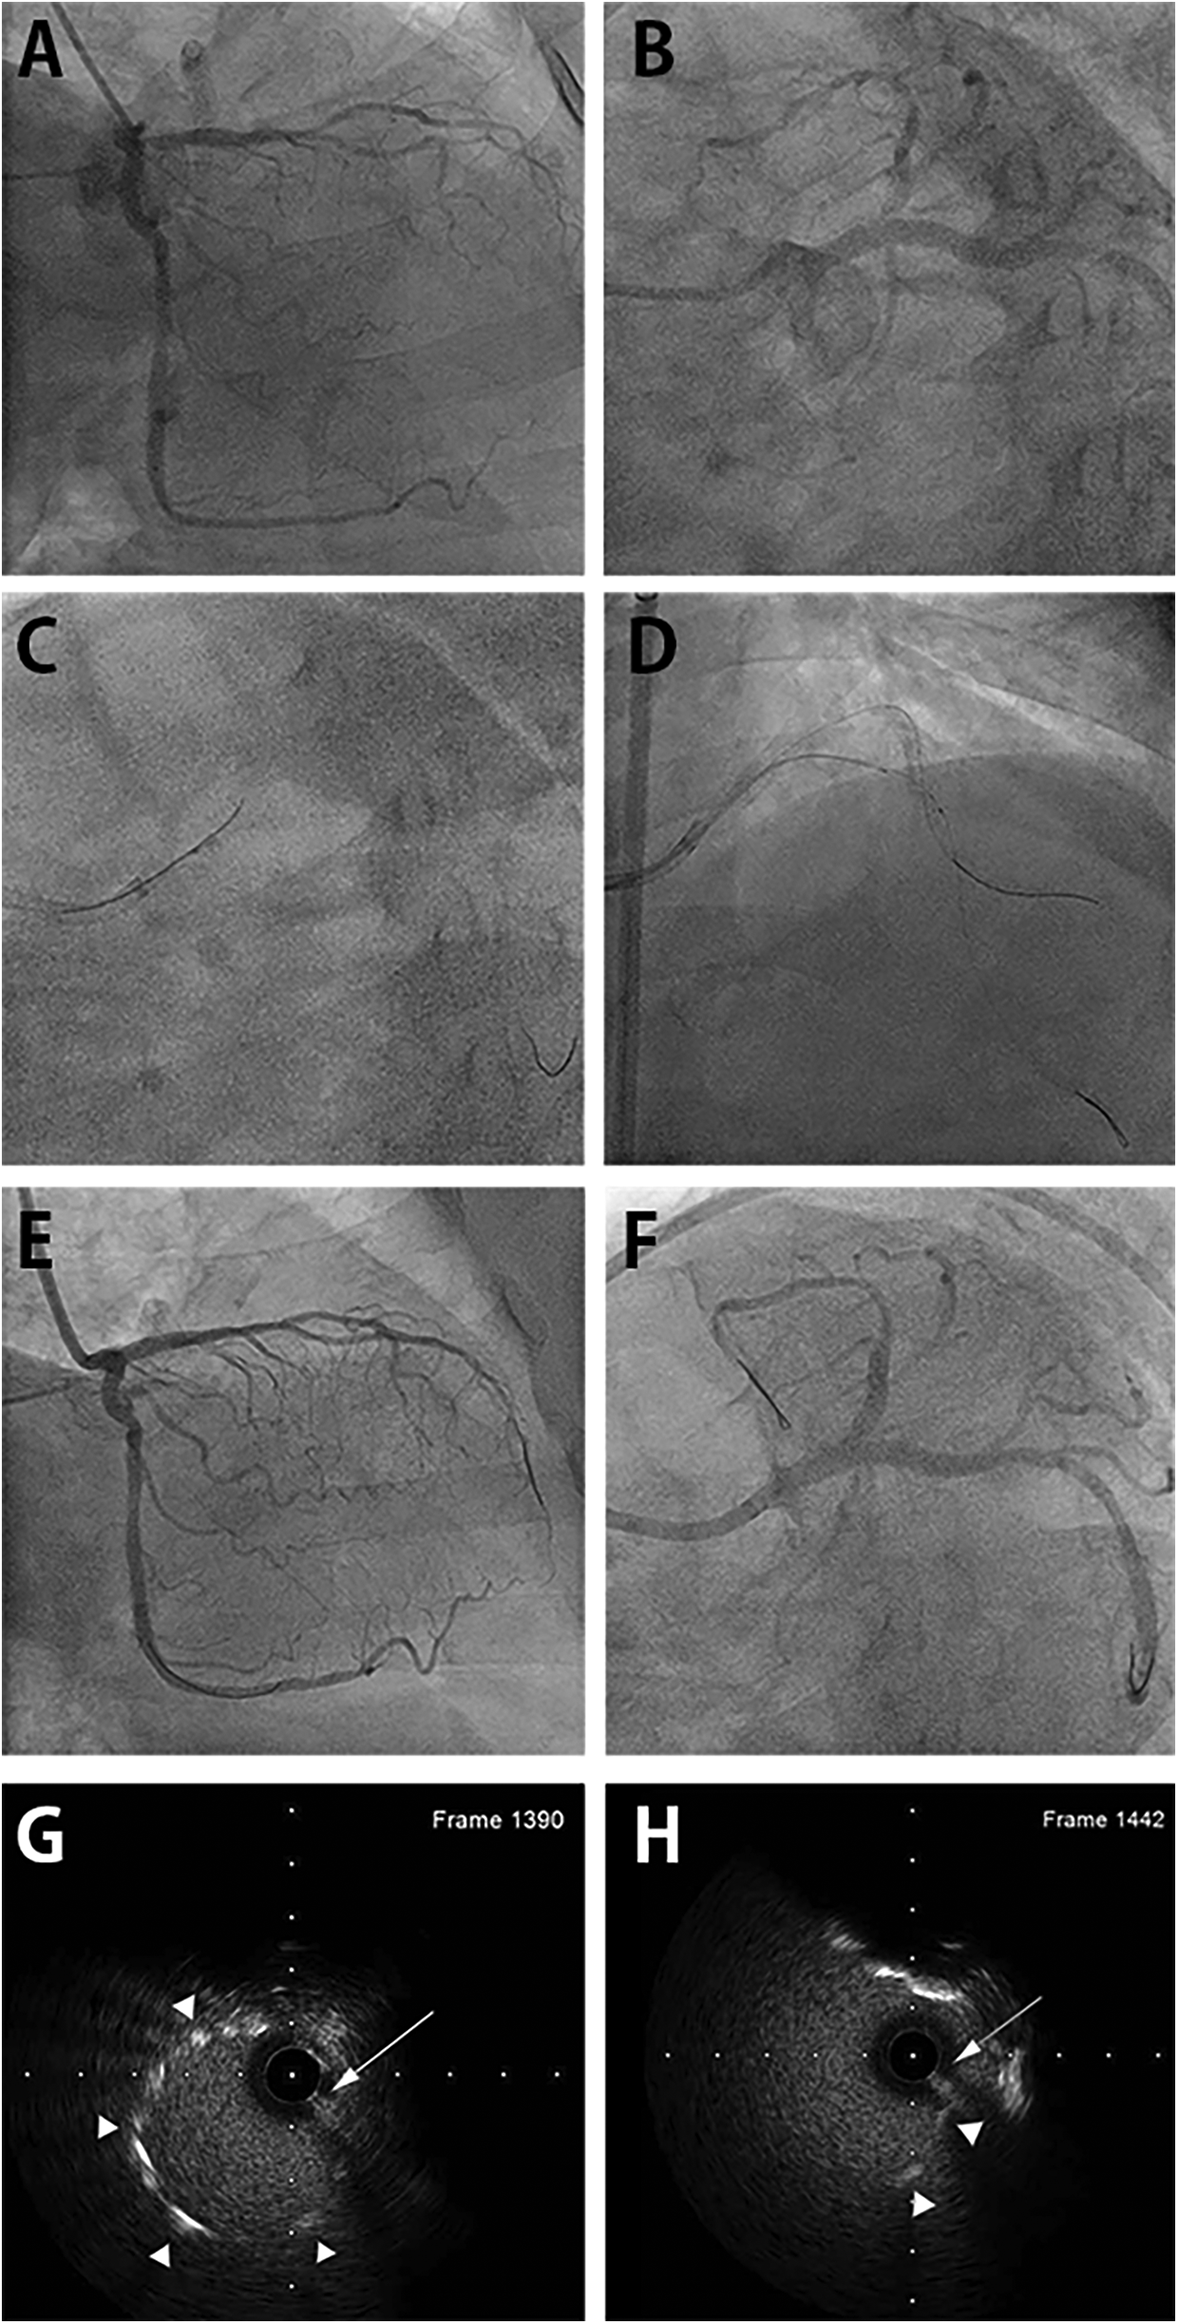

Figure 2

DLC-facilitated aorto-ostial wiring technique in the left main coronary artery. (A) Coronary angiography with a misaligned catheter from the right anterior oblique caudal view demonstrates a tight ostial stent in the left anterior descending artery and a patent stent spanning from the left main to the left circumflex artery. (B) The left anterior oblique caudal view exhibits the same finding, with the catheter tip placed next to the protruding aorto-ostial stent. (C) DLC is loaded onto the first wire and anchored at the protruding stent strut. The second wire enters the central stent lumen. (D) The wire's central position is confirmed by IVUS. (E) The final angiography from the right anterior oblique caudal view after stenting shows acceptable angiographic results with proper coaxial engagement of the guiding catheter. (F) Angiography from the left anterior oblique caudal view demonstrates a well-expanded stent with the coaxial position of the guiding catheter. (G) IVUS image revealing luminal position of second wire in the mid portion of the protruding stent outside the coronary artery. First wire was retracted before IVUS imaging. (H) IVUS image showing luminal position at the very proximal end of protruding stent. DLC, dual-lumen microcatheter; IVUS, intravascular ultrasound. (Arrows indicate second wire. Arrowheads indicate stent strut.)